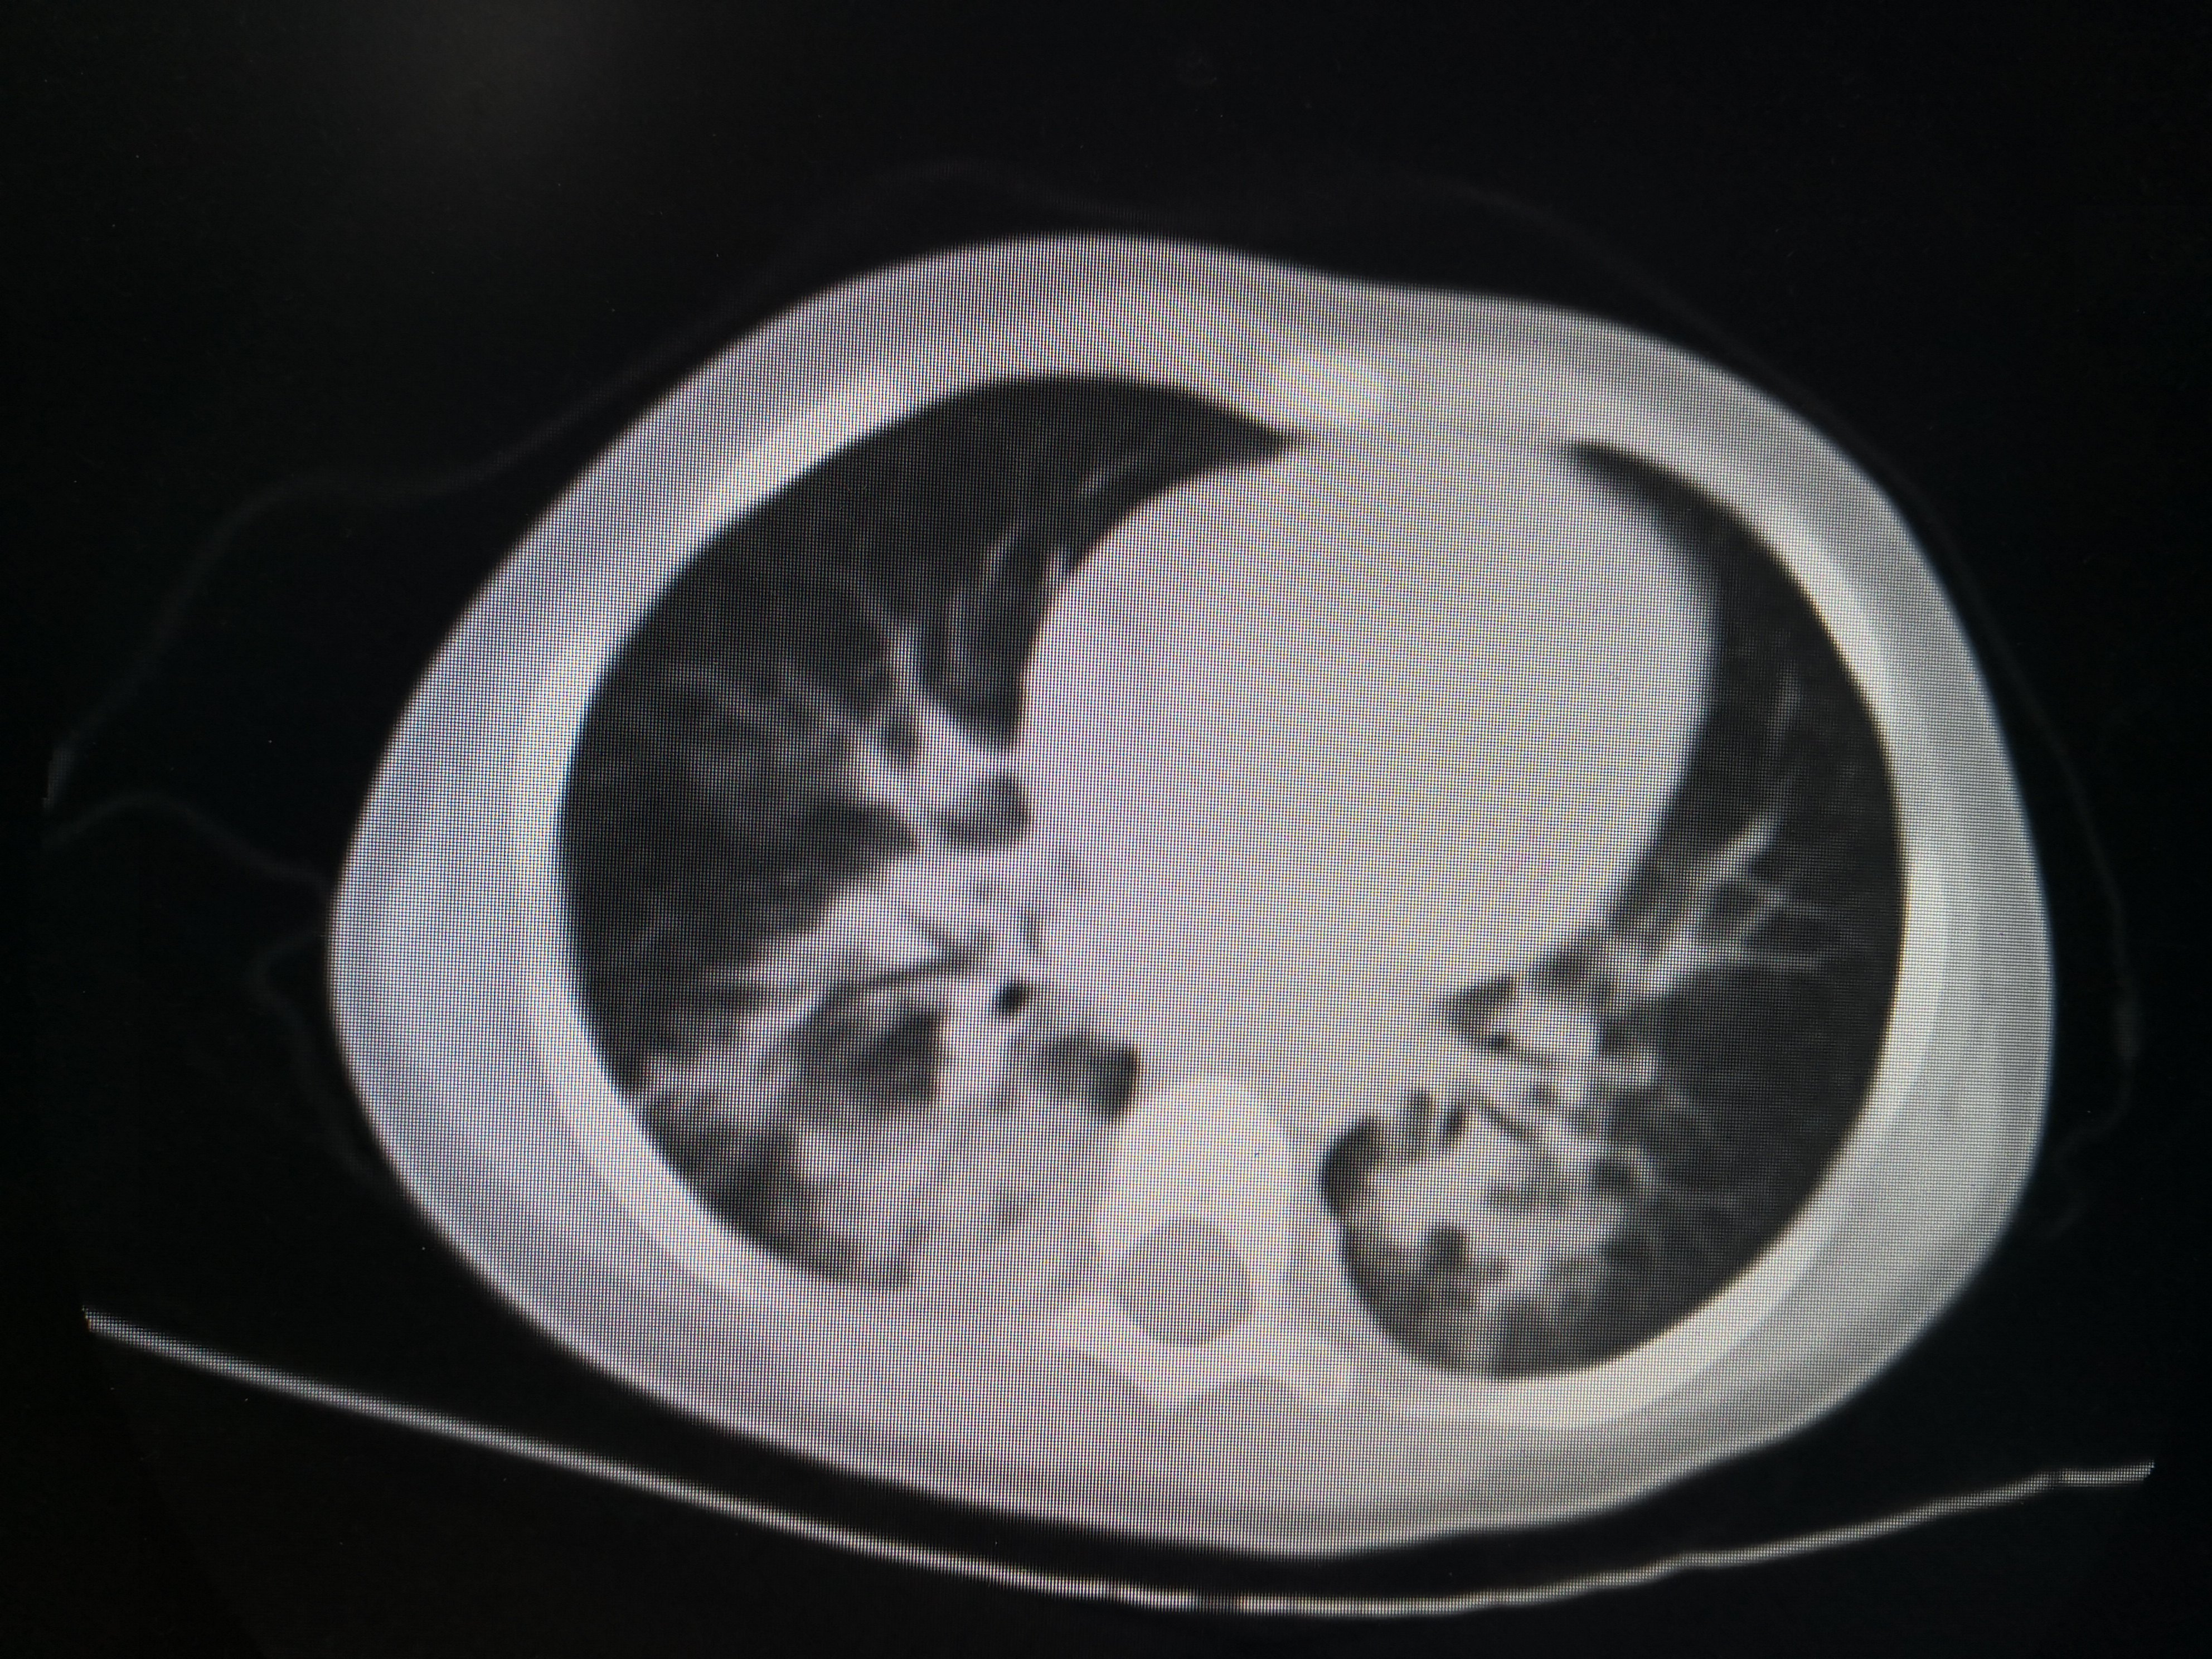

某小朋友1岁多,家住农村,在玩耍的时候不慎坠入粪池,该粪池深1.5米,不到一分钟该小朋友就已经被粪池漫过头顶仅剩一只手在外面,幸运的是旁边有大人及时发现并立即将其从粪坑里拔出。但是整个救援过程将近10分钟,小朋友被救出时已经失去意识,处于昏迷状态,急诊送至当地县医院清洗后立即120送至重庆医科大学附属儿童医院呼吸一科。入院时小朋友已经清醒,但是高烧不退,炎症指标非常高!入院后积极予以强有力的抗生素抗感染,并完善胸部CT评估双肺吸入性肺炎的严重程度,如图1

双肺炎症非常明显。CT结果出来后立即予以支气管镜灌洗治疗,在灌洗治疗过程中发现小朋友气管支气管里面大量黑色粪渣伴有较多黄色粪汁,遂将每个肺叶肺段灌洗干净,一周内完成2次支气管镜的灌洗治疗。第二次灌洗的时候双肺已经比较干净。出院后又口服了两周的强力抗生素。两周后复查胸部CT,结果如下